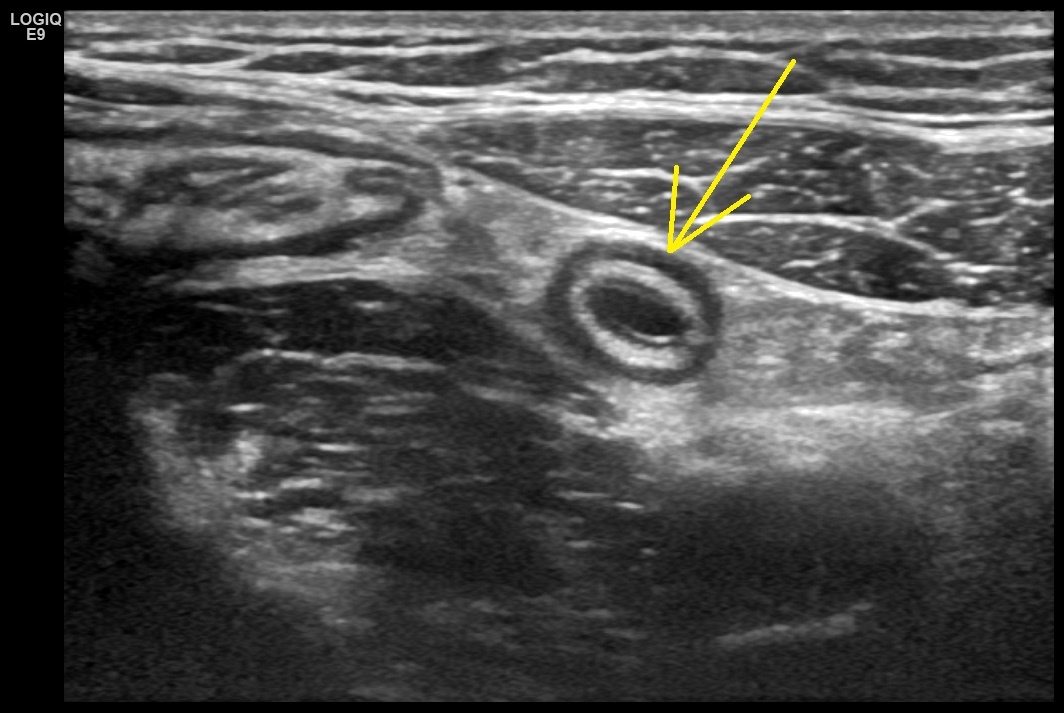

В правой подвздошной области, кпереди от контура большой поясничной мышцы, в типичном месте лоцируется аппендикс, утолщенный до 8-10 мм.

Рис. 01. Аппендикс, поперечное изображение.

Стенки аппендикса утолщены, преимущественно за счет утолщения и инфильтрации гиперэхогенного подслизистого слоя. В просвете определяется однородная жидкость.